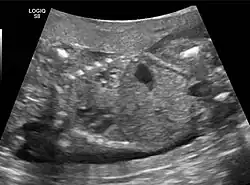

CPAMs are often identified during routine prenatal ultrasonography. Identifying characteristics on the sonogram include: an echogenic (bright) mass appearing in the chest of the fetus, displacement of the heart from its normal position, a flat or everted (pushed downward) diaphragm, or the absence of visible lung tissue.

The earliest point at which a CPAM can be detected is by prenatal ultrasound. The classic description is of an echogenic lung mass that gradually disappears over subsequent ultrasounds. The disappearance is due to the malformation becoming filled with fluid over the course of the gestation, allowing the ultrasound waves to penetrate it more easily and rendering it invisible on sonographic imaging. When a CPAM is rapidly growing, either solid or with a dominant cyst, they have a higher incidence of developing venous outflow obstruction, cardiac failure and ultimately hydrops fetalis. If hydrops is not present, the fetus has a 95% chance of survival. When hydrops is present, risk of fetal demise is much greater without in utero surgery to correct the pathophysiology. The greatest period of growth is during the end of the second trimester, between 20 and 26 weeks.